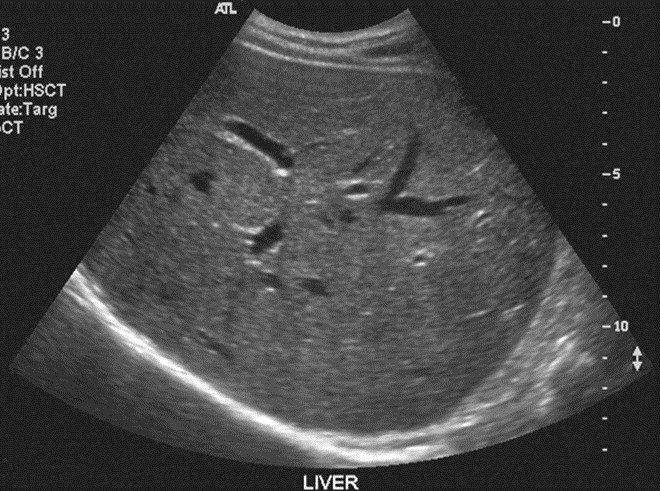

B-mode ultrasound: The standard grayscale imaging mode where echo amplitude determines pixel brightness.

A typical B-mode ultrasound showing liver anatomy with visible internal structures and the bright diaphragm interface.